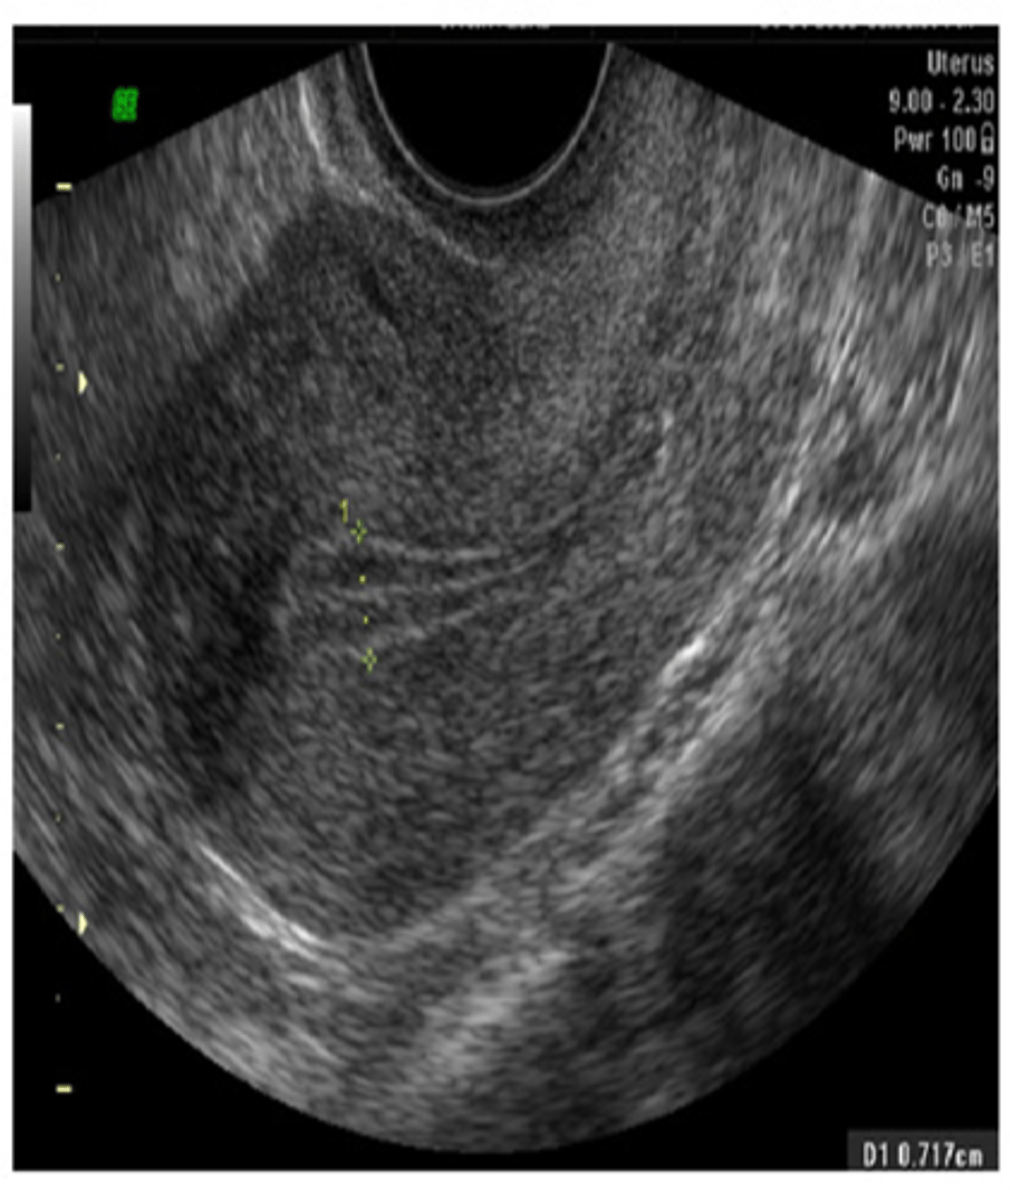

During the menstrual phase, the endometrium appears ___ and ___

thin; bright

During the early proliferative phase, the endometrium appears ___ and measures ___

bright; 4-8 mm

During the late proliferative phase, the ___ is visible and endometrium thickens to ___

3 line sign; 6-10 mm

During the secretory phase, the endometrium appears ___ and ___ and measures ___

thick; echogenic; 7-14 mm